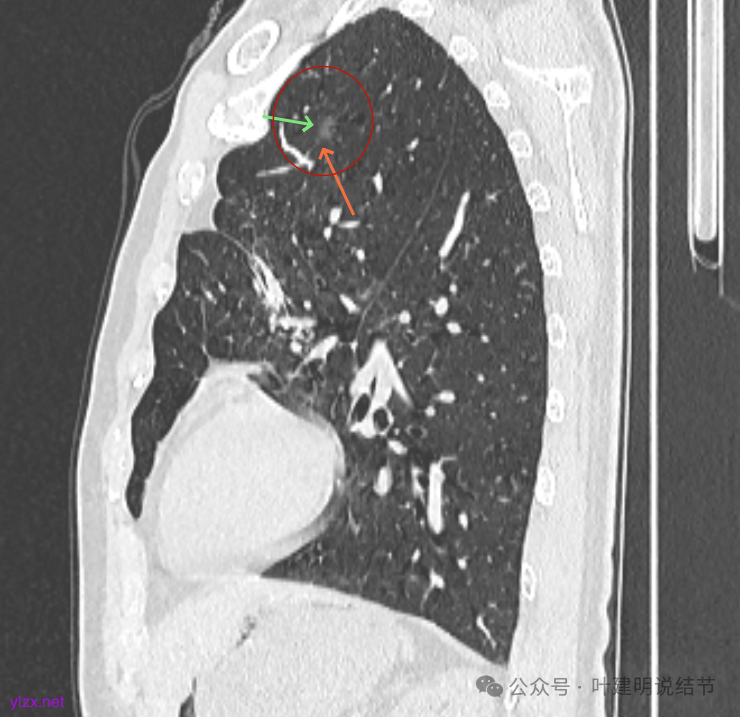

最后看2025年3月的连续层面的影像细节:

左上病灶淡而纯,有微小血管进入。

左上的小而局部有细支气管扩张的样子,部分边缘显毛糙,有细毛刺样征。

右上叶病灶有血管贴边,轮廓清;

左上病灶纯磨,轮廓清。

右上淡磨,左下密度较右侧的稍不均一点。

左上病灶矢状位见也是纯的,没有实性成分。